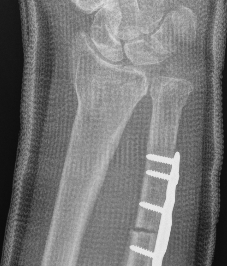

Xray

Bilateral xrays

PA film in neutral

- wrist neutral

- elbow & shoulder at 90°

CT

Distal radial osteotomy

Indications

Dorsal tilt / radial tilt / loss of inclination

Acceptable DRUJ articular surface

Dorsal opening wedge osteotomy

Advantage

Lengthens the distal radius

May be easier to correct in coronal and sagittal plane

Disadvantage

Dorsal approach / dorsal plate - extensor tendon issues